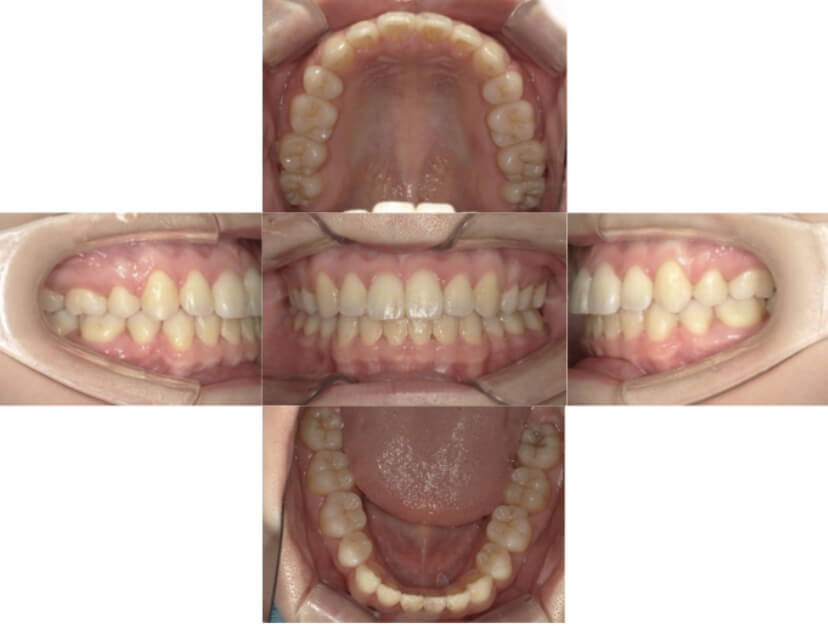

症例3

叢生

抜歯

ブラケット矯正

上下顎叢生(上下の前歯のガタガタ)のケースです。

装置はラビアル(上下表側)で、上下顎の小臼歯を4本抜歯を行っています。抜歯したスペースを使って、上下の前歯の後方移動と叢生(ガタガタ)の改善を行っています。

主訴 八重歯を治したい。

年齢・性別 25歳 女性

お住まいの地域 神奈川県川崎市

治療方針 抜歯スペースを利用して上前歯の叢生(ガタガタ)の改善

抜歯部位 上下顎左右第一小臼歯

使用装置 ラビアル(上下表側)、顎間ゴム

治療期間 1年11か月

治療回数 16回

リテーナー クリアリテーナー

BEFORE

AFTER